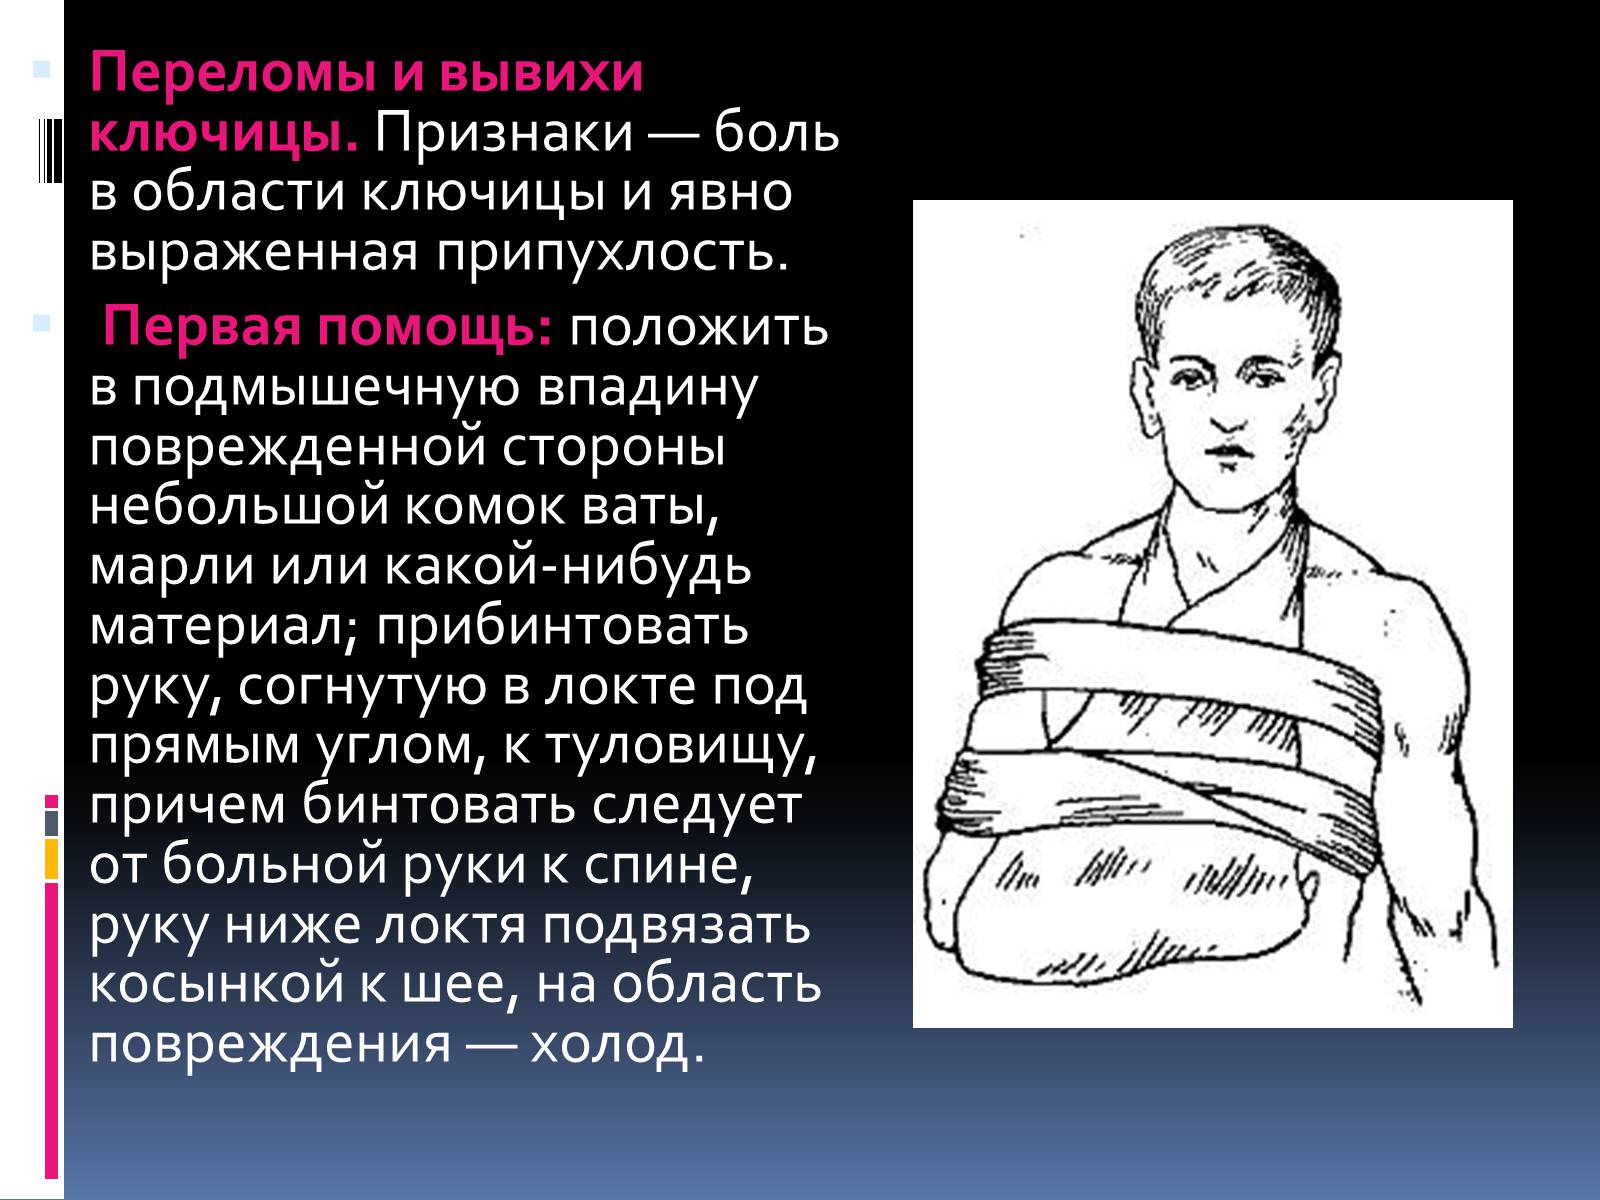

Вывихи и переломы ключицы презентация - 85 фото